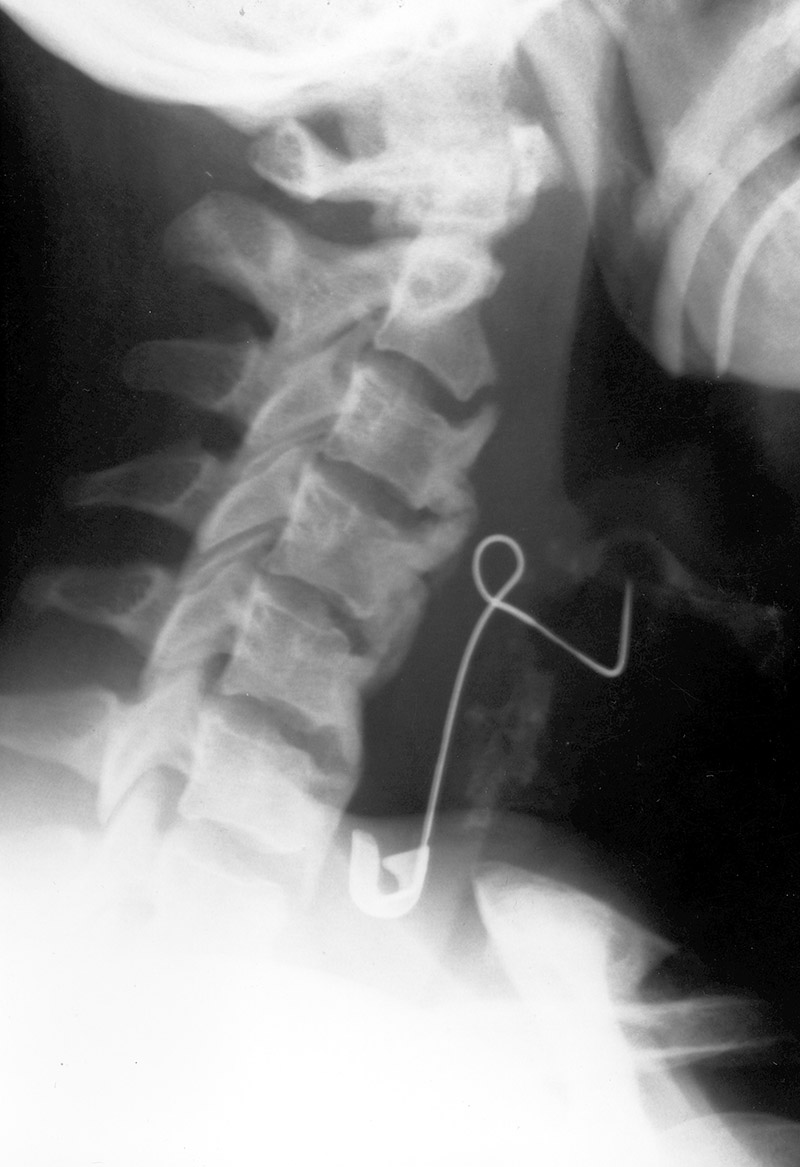

37 year-old mentally disabled woman who was admitted comatose with a 24-hour history of difficulty breathing. An open safety pin had perforated the wall of her esophagus and penetrated her larynx. It was extracted at laryngoscopy, and she recovered without sequelae. From Hunter, 1994 |